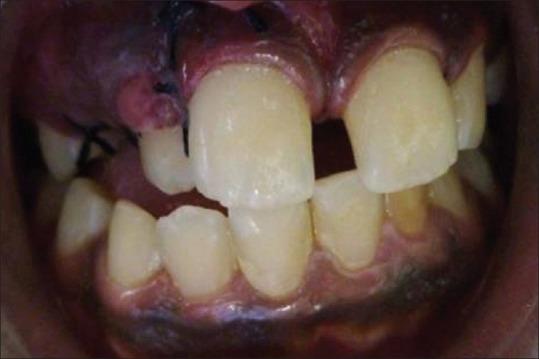

The simultaneous occurrence of hypodontia and supernumerary teeth in the same individual is termed as "concomitant hypohyperdontia" and it is an uncommon condition with the etiology still unknown. Presented here is a very rare case of simultaneous presence of multiple supernumerary teeth and multiple missing teeth (bilateral maxillary second premolars and bilateral mandibular second molars) involving both jaws with a history of subclinical hypothyroidism. Systemic diseases could probably play a role in the etiologic occurrence of co-existent partial anodontia and supernumerary teeth.

在同一个体中同时出现缺牙和多生牙的情况被称为“伴随性牙量过少与牙量过多”,这是一种罕见的病症,其病因尚不清楚。本文介绍了一例极为罕见的病例,该患者两颌均同时存在多个多生牙和多个牙齿缺失(双侧上颌第二前磨牙和双侧下颌第二磨牙),并有亚临床甲状腺功能减退病史。全身性疾病可能在并存的部分无牙症和多生牙的病因发生中起作用。